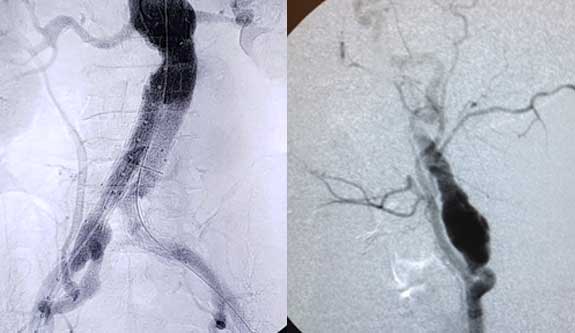

Aneurismas Arteriais

caracterizados pela dilatação de uma ou mais artérias, excedendo em 50% o diâmetro normal do vaso. Dentre as suas principais causas encontram-se o tabagismo….